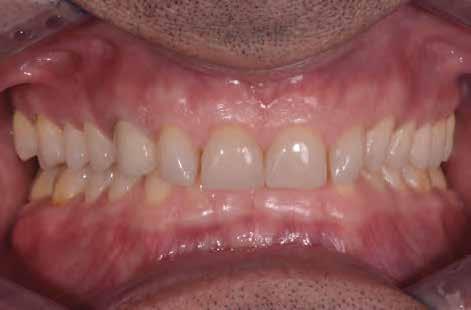

1. ábra: A beteg esztétikai problémájára kért megoldást a régi restaurációk természetellenes megjelenése, továbbá a múltban lezajlott periodontitis következtében kialakult fekete háromszögek miatt. A szövetek visszahúzódása következtében a fogpótlás széle jól láthatóvá vált, a papilla csúcsok elvesztése és a koronák közötti számos fekete térrel együtt, komplex terápiás ellátást igényelt.

2. ábra: A parodontális problémák nem sebészeti kezelési terve a következőkből állt: fogkő-eltávolítás és gyökérsimítás, a korábbi rögzített fogpótlás cseréje, a marginális szövetek helyreállítása, és egy új, esztétikailag kedvezőbb gingivális szerkezet helyreállításának megkönnyítése.

Funkcionális szempontból úgy döntöttünk, hogy redukáljuk a mély frontharapást, a korrekt overjet/overbite arány helyreállításához. A redukció esztétikai szempontból is fontos volt, hogy lehetővé tegye számunkra a különböző alkotóelemek helyes kialakítását.

16. ábra: Klinikai fotó egy évvel a PANAVIA V5-tel történő beragasztás után. A marginális szövetek jó klinikai állapotát látjuk, semmi jele gyulladásnak vagy vérzésnek. A BOPT lehetővé teszi számunkra, hogy optimalizáljuk a gingiva szintjét anélkül, hogy parodontológiai sebészeti beavatkozáshoz folyamodnánk, miközben az új koronák alakja lehetővé tette az interproximális terek zárását az optimális esztétikai eredmény érdekében.

17. ábra: A fogpótlás világossága (főleg a transzlucentes cirkónium használatának köszönhetően), a metszők alakjával kombinálva nagymértékben javította a pótlás esztétikáját, még akkor is, ha a kiindulási helyzet különösen kedvezőtlennek tűnt.

18. ábra: Az előző fogpótlással összehasonlítva a metszők redukálása nem csak azt tette számunkra lehetővé, hogy optimalizáljuk a funkcionális fázist az overjet csökkentésével, hanem lehetővé tette a még esztétikusabb eredmény elérését azzal, hogy a metszők élének kontúrjával követni tudtuk az alsó ajkat.